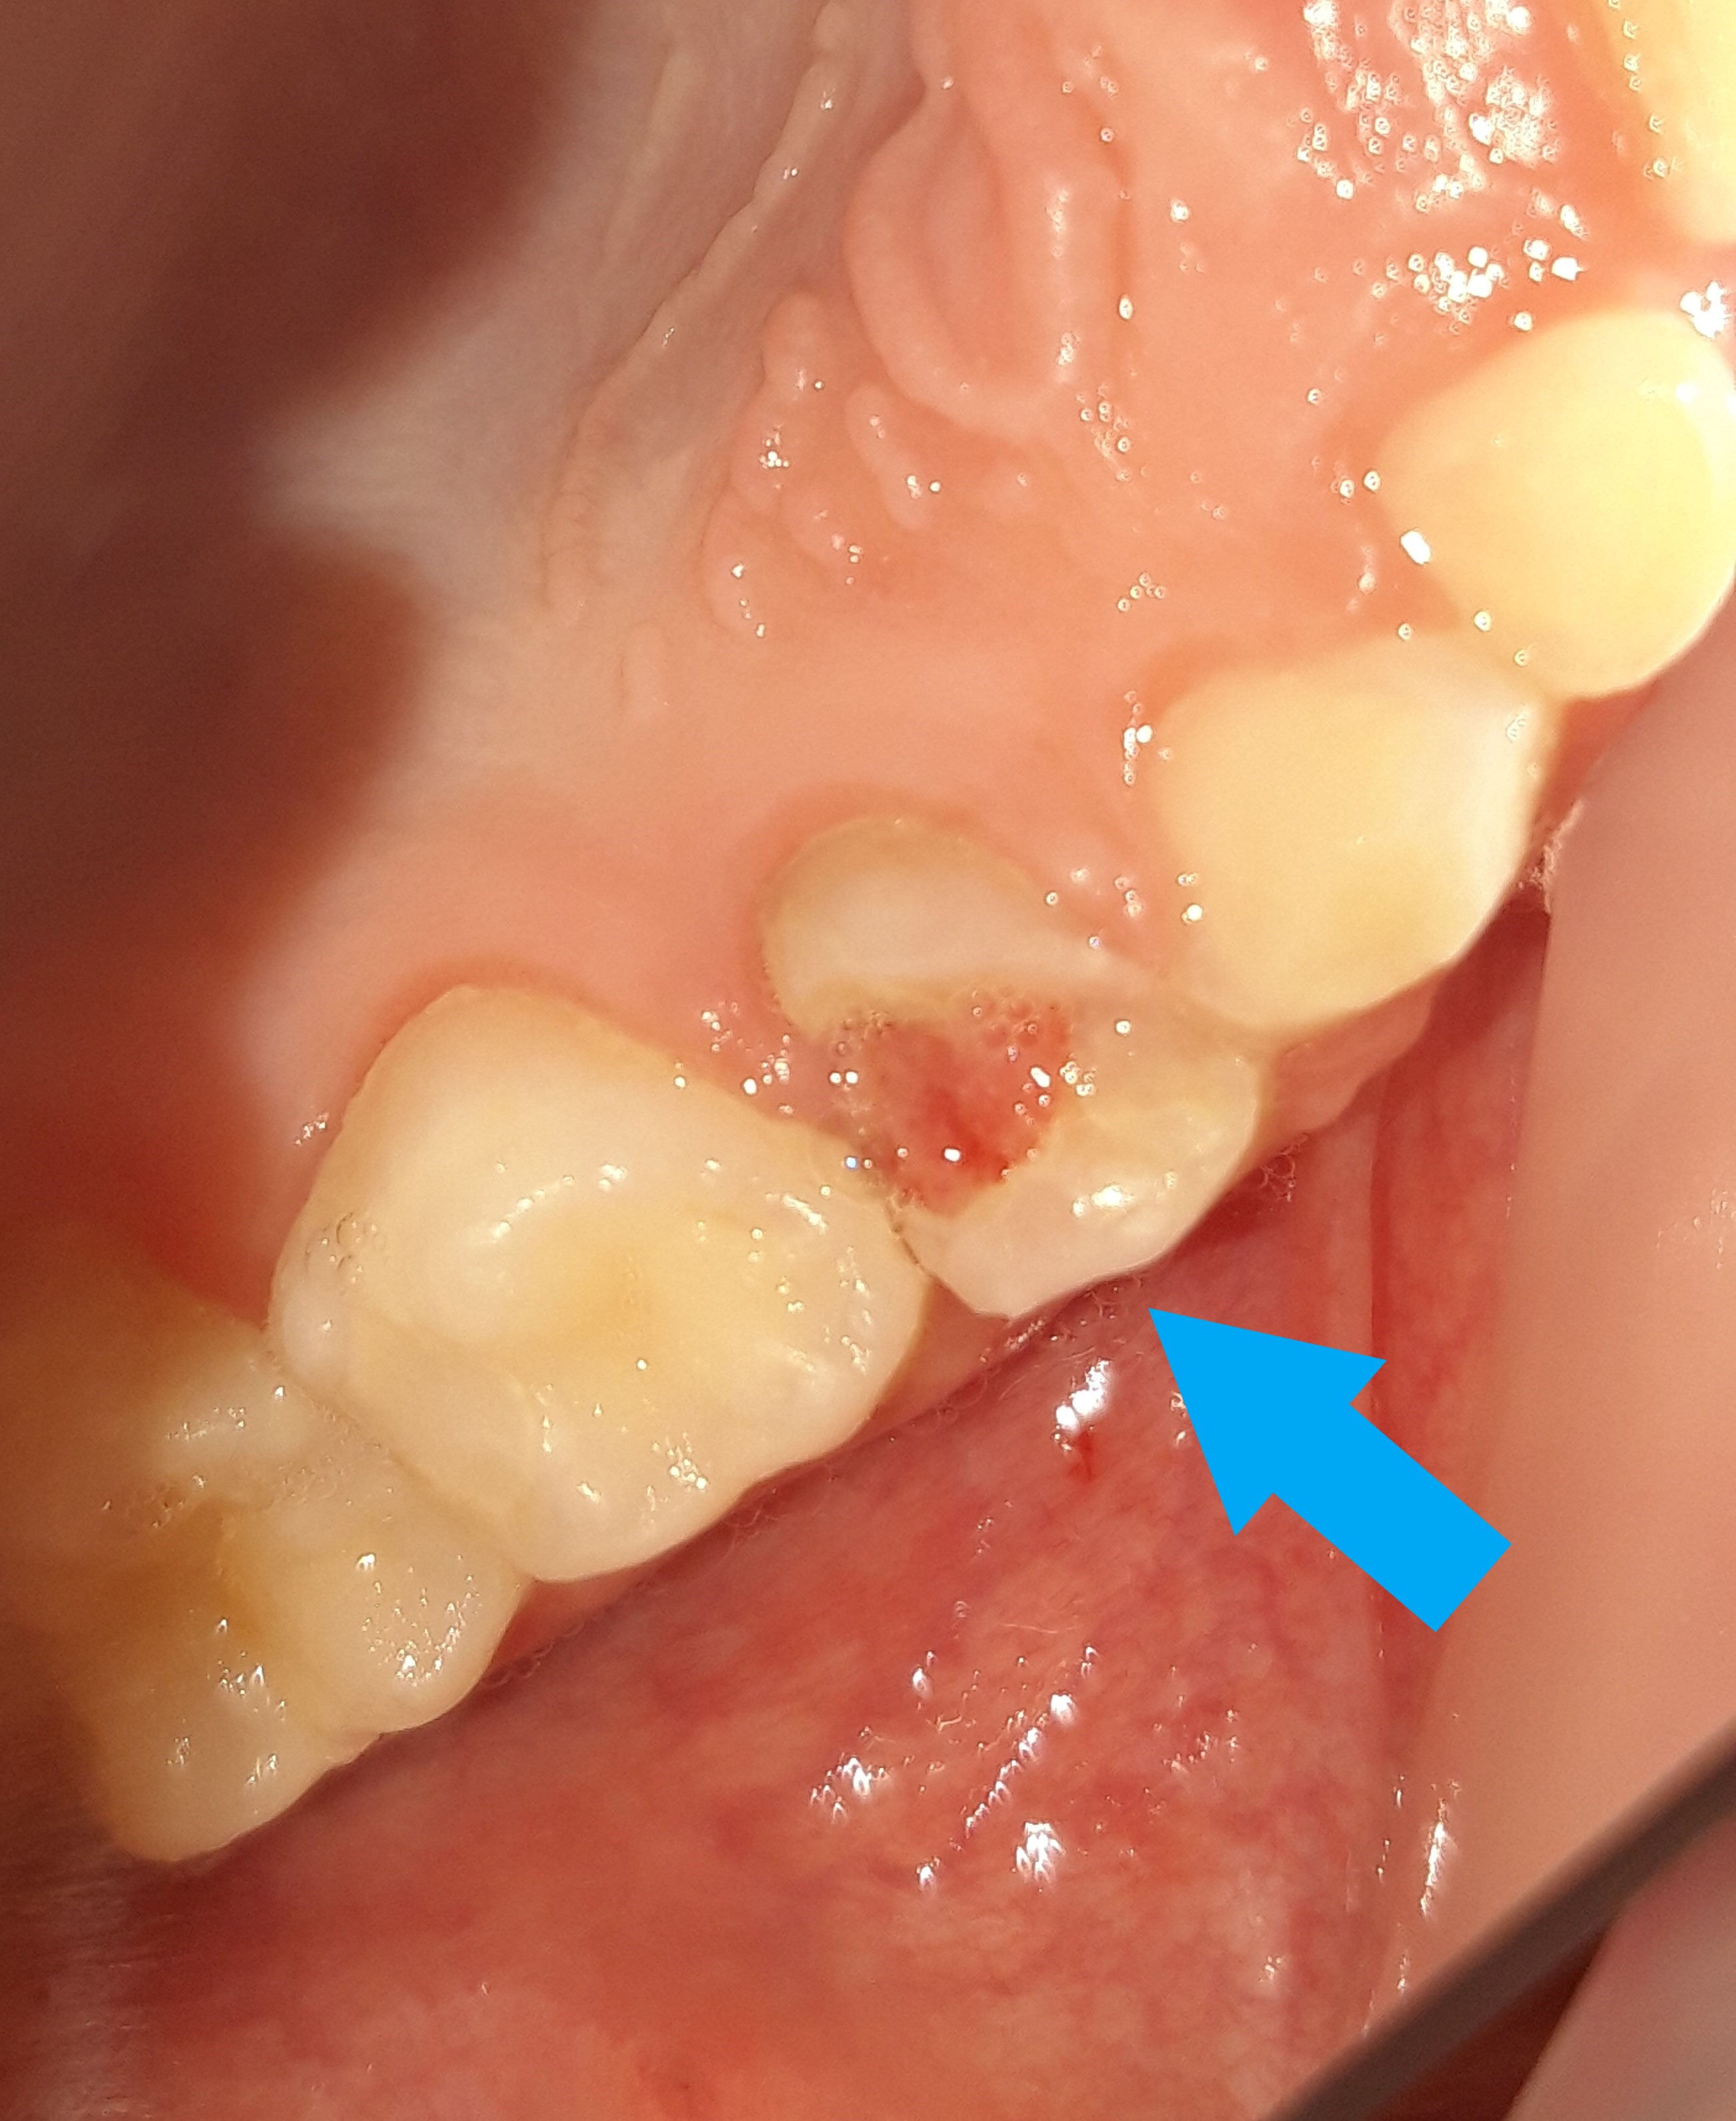

Περιστατικό – Συρίγγιο σε παιδικό δόντι

Το παιδί προσήλθε στο ιατρείο καθώς η μητέρα του όπως είπε εμφάνισε στο στόμα του ένα σπυράκι. Μετά την κλινική εξέταση του παιδιού διαπιστώθηκε οτι το “σπυράκι” ήταν απόστημα το οποίο οφειλόταν στο βαθύ τερηδονισμό και μόλυνση ενός πίσω παιδικού δοντιού. Το δοντάκι δεν μπορούσε να διατηρηθεί στο στόμα και η θεραπεία επιλογής ήταν η εξαγωγή του παιδικού δοντιού. Σε δεύτερο χρόνο το παιδί θα πρέπει να επισκεφτεί ορθοδοντικό για τη διατήρηση του απαιτούμενου χρόνου με σκοπό την απρόσκοπτη ανατολή του αντίστοιχου μόνιμου δοντιού.